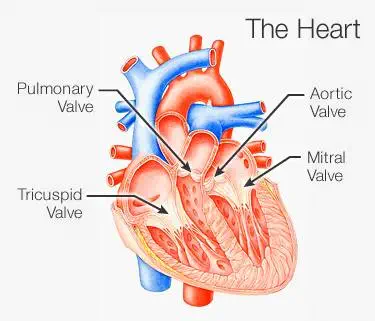

قلب دارای چهار دریچهی آئورت (aortic)، میترال (mitral)، ریوی (pulmonary) و دریچه سهلتی (س...

تعریف بیماری قلبی

بیماری قلبی، طیف وسیعی از شرایط را توصیف میکند که قلب شما را تحت تاثیر...